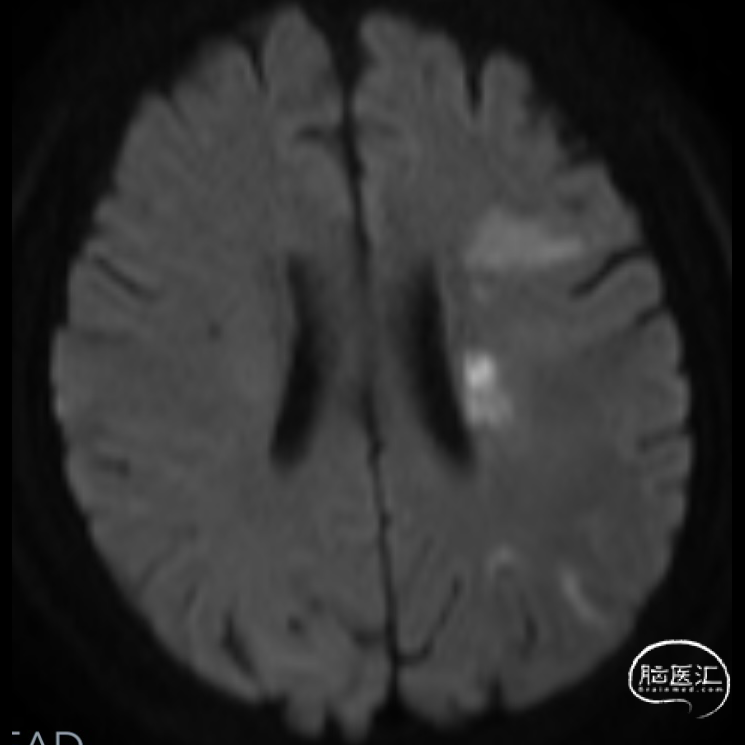

➤2024.2.28 头颅MRI+MRA

左额顶叶/左枕叶亚急性期脑梗死,左侧大脑中动脉M1段重度狭窄。

➤2024.3.20 头颅MRI

左侧基底节区/侧脑室旁及额顶枕叶急性期脑梗死。